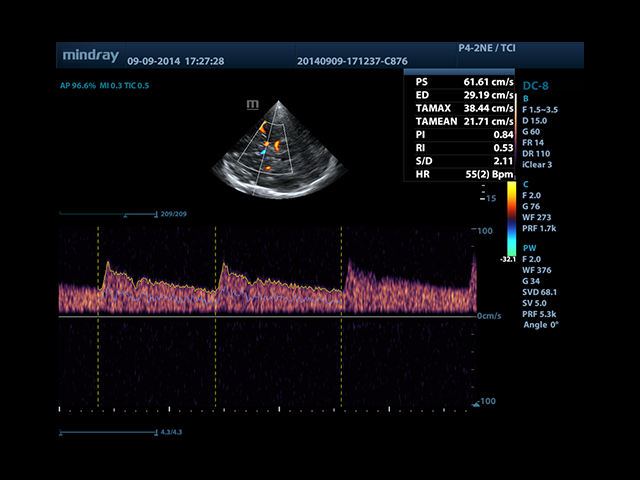

• Smart Doppler - автоматическая подстройка расположения рамки цветового доплера и контрольного объема импульсно-волнового доплера нажатием кнопки.

• Автоматическая трассировка допплеровского спектра с расчетом параметров и индексов

• Smart Doppler™ - автоматическая подстройка расположения рамки цветового допплера и контрольного объема импульсно-волнового допплера